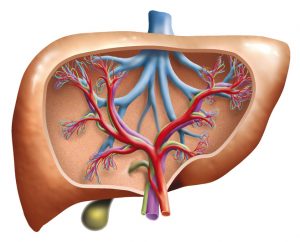

When the bile ducts become destroyed, harmful substances start building up in the liver, contributing to irreversible scarring.

As mentioned, because PBC is an autoimmune disease, the exact cause is unknown. How PBC can develop due to inflammation resulting from the accumulation of T cells within the liver as an immune response.

Normally, T cells recognize danger and work to defend the body, but in PBC, they wrongfully attack and destroy the cells of the biliary ducts within the liver.

Over time, inflammation starts spreading and healthy tissues get replaced with scar tissues, contributing to cirrhosis.

Complications that can arise as a result of PBC include cirrhosis, increased pressure in the portal veins, enlarged spleen, gallstones, enlarged veins, liver cancer, weak bones, vitamin deficiencies, decreased mental function, and an increased risk of other diseases such as metabolic syndrome and immune disorders like thyroid problems.